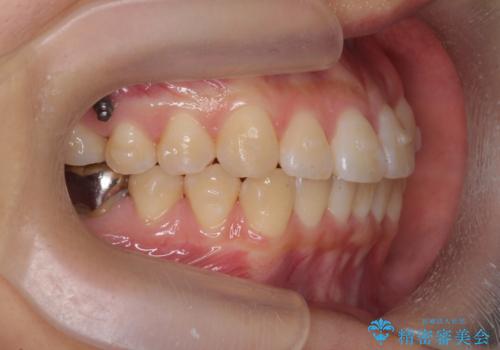

正中のズレ、引っ込んだ前歯の矯正

- 噛んだ時の前歯正中のズレ、引っ込んでいる前歯を治したい。と矯正治療を希望され来院されました。

左上2の前歯はスペースが足りないため、後方に引っ込んでしまっている状態です。

マウスピース矯正システムインビザラインで歯の後方移動、咬合関係の修正を行ったのち、引っ込んでいる左上2をワイヤーを用いて短時間で引き出す治療計画としました。

部分ワイヤー矯正を行なったことで約3ヶ月という短期間で前歯を綺麗に並べることができました。